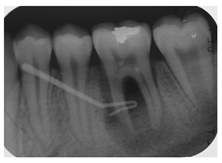

| 3 | A 29-year-old patient visits the dental clinic to evaluate his/her general oral state. A complete clinical examination is carried out and no pathological signs were observed. Bitewing x-rays are performed, and various radiolucent lesions limited to the enamel were observed on the right bitewing x-ray. | ![]() | Select the most adequate treatment alternative for tooth 4.6 from the answers provided. |

| [13,14] | |